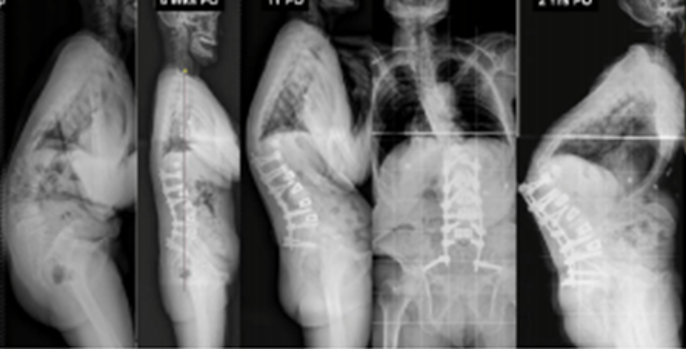

图7 术前-术后1个月-术后1个月外观